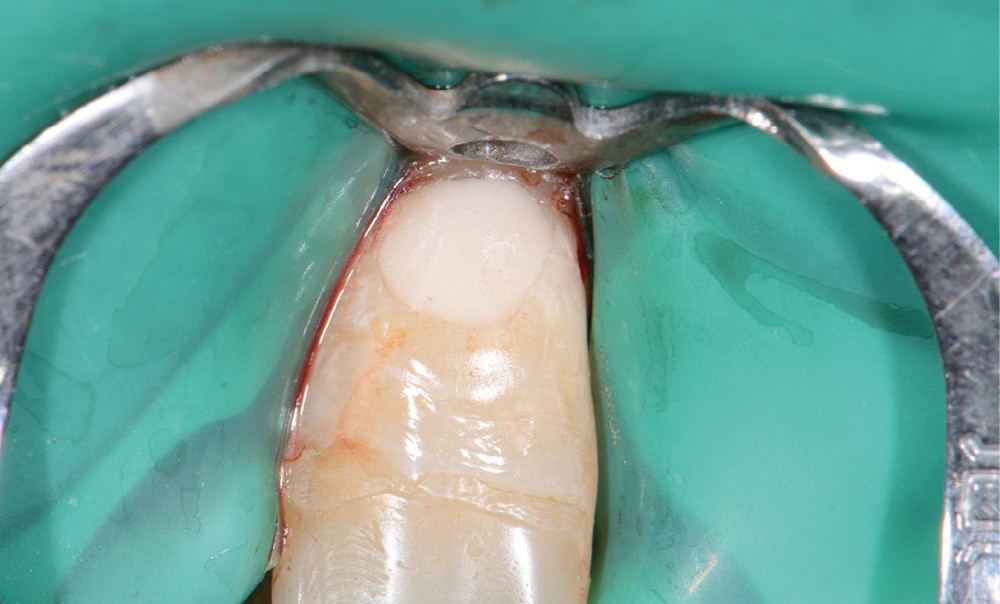

Perforation infra-osseuse avec accès visuel direct (fig. 3)

Ce type de perforation est également la plupart du temps iatrogénique et survient lors de la recherche ou de la mise en forme canalaire, lors de la préparation pour un logement de tenon radiculaire. Situées au niveau du plancher pulpaire des dents pluriradiculées, ou au niveau des entrées canalaires des dents monoradiculées ou pluriradiculées, il s’agit le plus souvent de perforations à quatre parois. Si la perforation survient en cours de traitement, elle doit être gérée immédiatement pour un meilleur pronostic (fig. 4). Néanmoins, il est important de prendre en compte l’épaisseur résiduelle du plancher. Si le plancher est trop fin, il ne sera pas possible d’envisager de traiter la perforation.